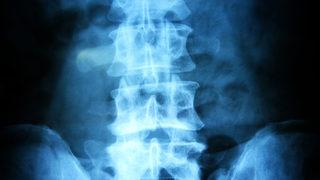

Bel fıtığı, günümüzde birçok insanın karşılaştığı yaygın bir sağlık sorunu olarak dikkat çekiyor. Bu sayfada, bel fıtığı haberleri ile birlikte, hastalığın sebepleri, tedavi yöntemleri ve en son gelişmeleri bulabilirsiniz. Yazılarımızda, son dakika bel fıtığı haberi ve güncel bel fıtığı haberleri gibi benzersiz içerikler sunarak okuyucularımızı bilgilendirmeyi amaçlıyoruz. Ayrıca, bu konuda uzman görüşlerine de yer vererek, tedavi süreçlerini ve iyileşme yollarını aktarma fırsatını bulacaksınız.

Son dönemde artan bel fıtığı vakaları ve bu konudaki tıbbi yenilikler, bu sorunla mücadelede önemli adımlar atılmasına neden oldu. Sayfamızdan, bel fıtığı ile ilgili en son gelişmelere ulaşabilir, sağlığınızı etkileyebilecek kritik bilgileri edinebilirsiniz. Güncel bel fıtığı haberleri ile her zaman dikkat çekecek bu alandaki yeniliklerden haberdar olmanız için sürekli güncellenen içeriklerimizi takip edin.